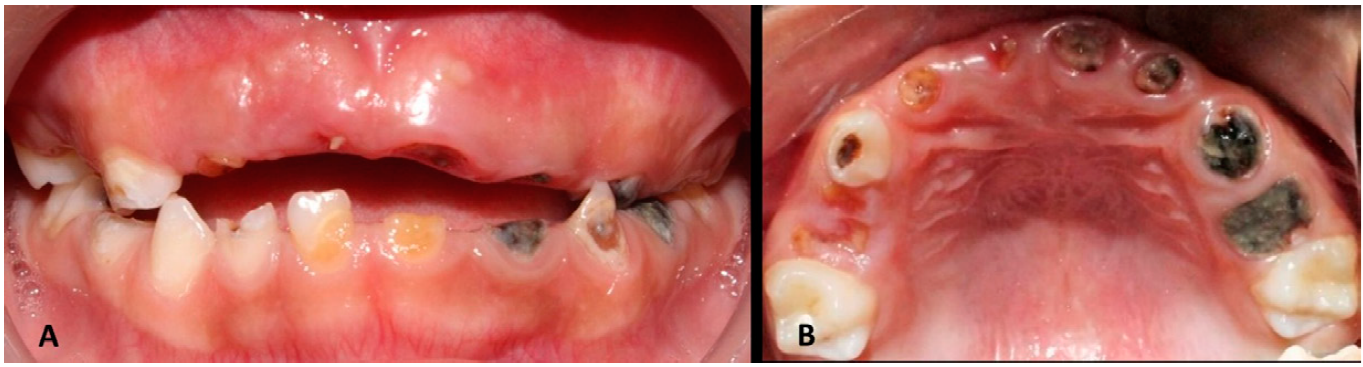

Las necesidades de salud oral en los infantes permiten conceptualizar el impacto que tiene un progenitor/cuidador sobre las condiciones orales pediátricas. Se ha descrito mayor presencia de índices de placa dentobacteriana, inflamación gingival, dientes con lesiones cariosas no tratadas e incluso una menor cooperación al momento de recibir tratamiento dental en niñas y niños que han sufrido algún tipo de abuso10. Por su parte, la caries dental, específicamente la caries de la infancia temprana (CIT- definida como la presencia de una o más lesiones cariosas, dientes perdidos u obturados antes de los 6 años) es la condición patológica oral más prevalente en la población pediátrica, con una estimación de su presencia en alrededor de 530 millones de niños a nivel mundial, según datos de la Organización Mundial de la Salud (OMS)11,12 (Figura 1.A-B). En México, el reporte sivepab (Sistema de Vigilancia de Patologías Bucales) en su versión más actual (2019), estima que, en la población mexicana de infantes de 2 a 5 años, un 70.3% presentan datos que sugieren que existe una alta necesidad de tratamiento de caries dental en la población pediátrica/adolescente mexicana13. El trauma dental/dentoalveolar, así como las lesiones faciales se han asociado a la presencia de abuso físico y sexual, debido a la naturaleza de los actos violentos14,15. Por otra parte, también las enfermedades gingivales/periodontales (especialmente en adolescentes y pacientes con compromisos sistémicos), son las otras condiciones que más afectan a esta población16.

Figura 1 Representación clínica de Caries de la Infancia Temprana - Las Caries de la infancia Temprana conllevan a una situación donde múltiples órganos dentarios se encuentren comprometidos y por consiguiente representan un riesgo al paciente pediátrico de padecer infecciones de origen odontogénico, odontalgia, dificultades para la masticación, nutrición y afectación a su calidad de vida. A. Vista frontal, B. Vista oclusal.